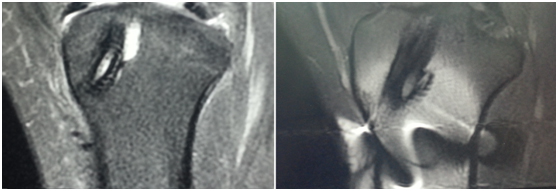

必须注意的是,即使体内的金属植入物被认为对于磁共振检查是安全的,也会产生一定伪影,在磁共振图像上表现为范围或大或小的“黑影”(低信号盲区)和图像扭曲失真,进而影响医生的诊断。一般来说,具有铁磁性的金属如不锈钢、镍铬合金、钴铬合金等产生的伪影比较严重,用于大关节置换的铝铜合金所导致的伪影也会对诊断有影响。而金片、纯银、纯钛、银汞合金、钛合金等金属植入物仅有轻度伪影,一般不会影响诊断

(左)没有明显金属伪影的磁共振图像和(右)金属植入物导致的低信号盲区和图像扭曲